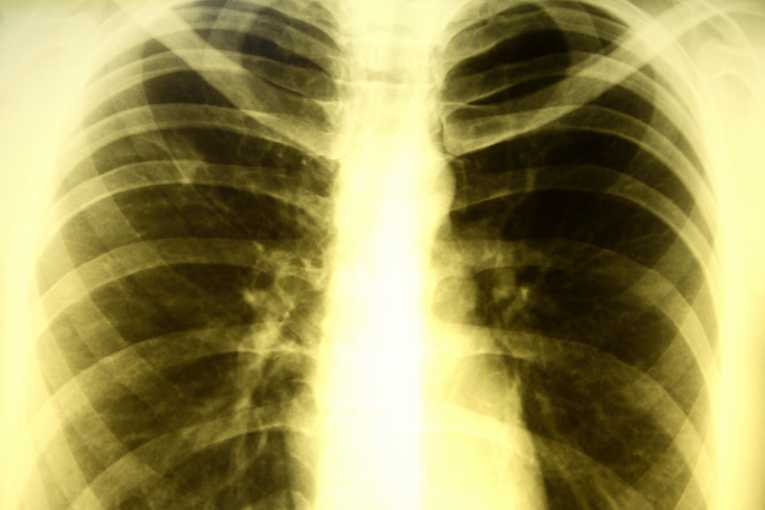

Despite years of anti-smoking efforts by public health officials, smoking remains a thriving habit throughout much of the world. Unfortunately, smoking is linked to an increased risk of contracting - and dying from - tuberculosis. About one-fifth of the global population presently smokes tobacco, and the number of smokers is expected to rise in coming decades, especially in the developing world.

The statistics are grim: Between 2010 and 2050, more than 18 million new cases of tuberculosis and in excess of 40 million deaths due to the respiratory infection.

The link between smoking and the risk of developing tuberculosis is so strong that public health officials have identified smoking cessation as a key goal of any viable program to eradicate tuberculosis.